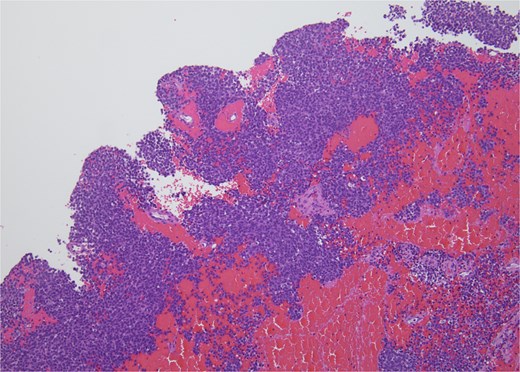

Histopathology revealed small, round, blue cells (Fig. 2), and other findings consistent with ES (Fig. 3).

H&E, 10×. The biopsy shows sheets of small round blue cells admixed with blood and fibrous tissue.